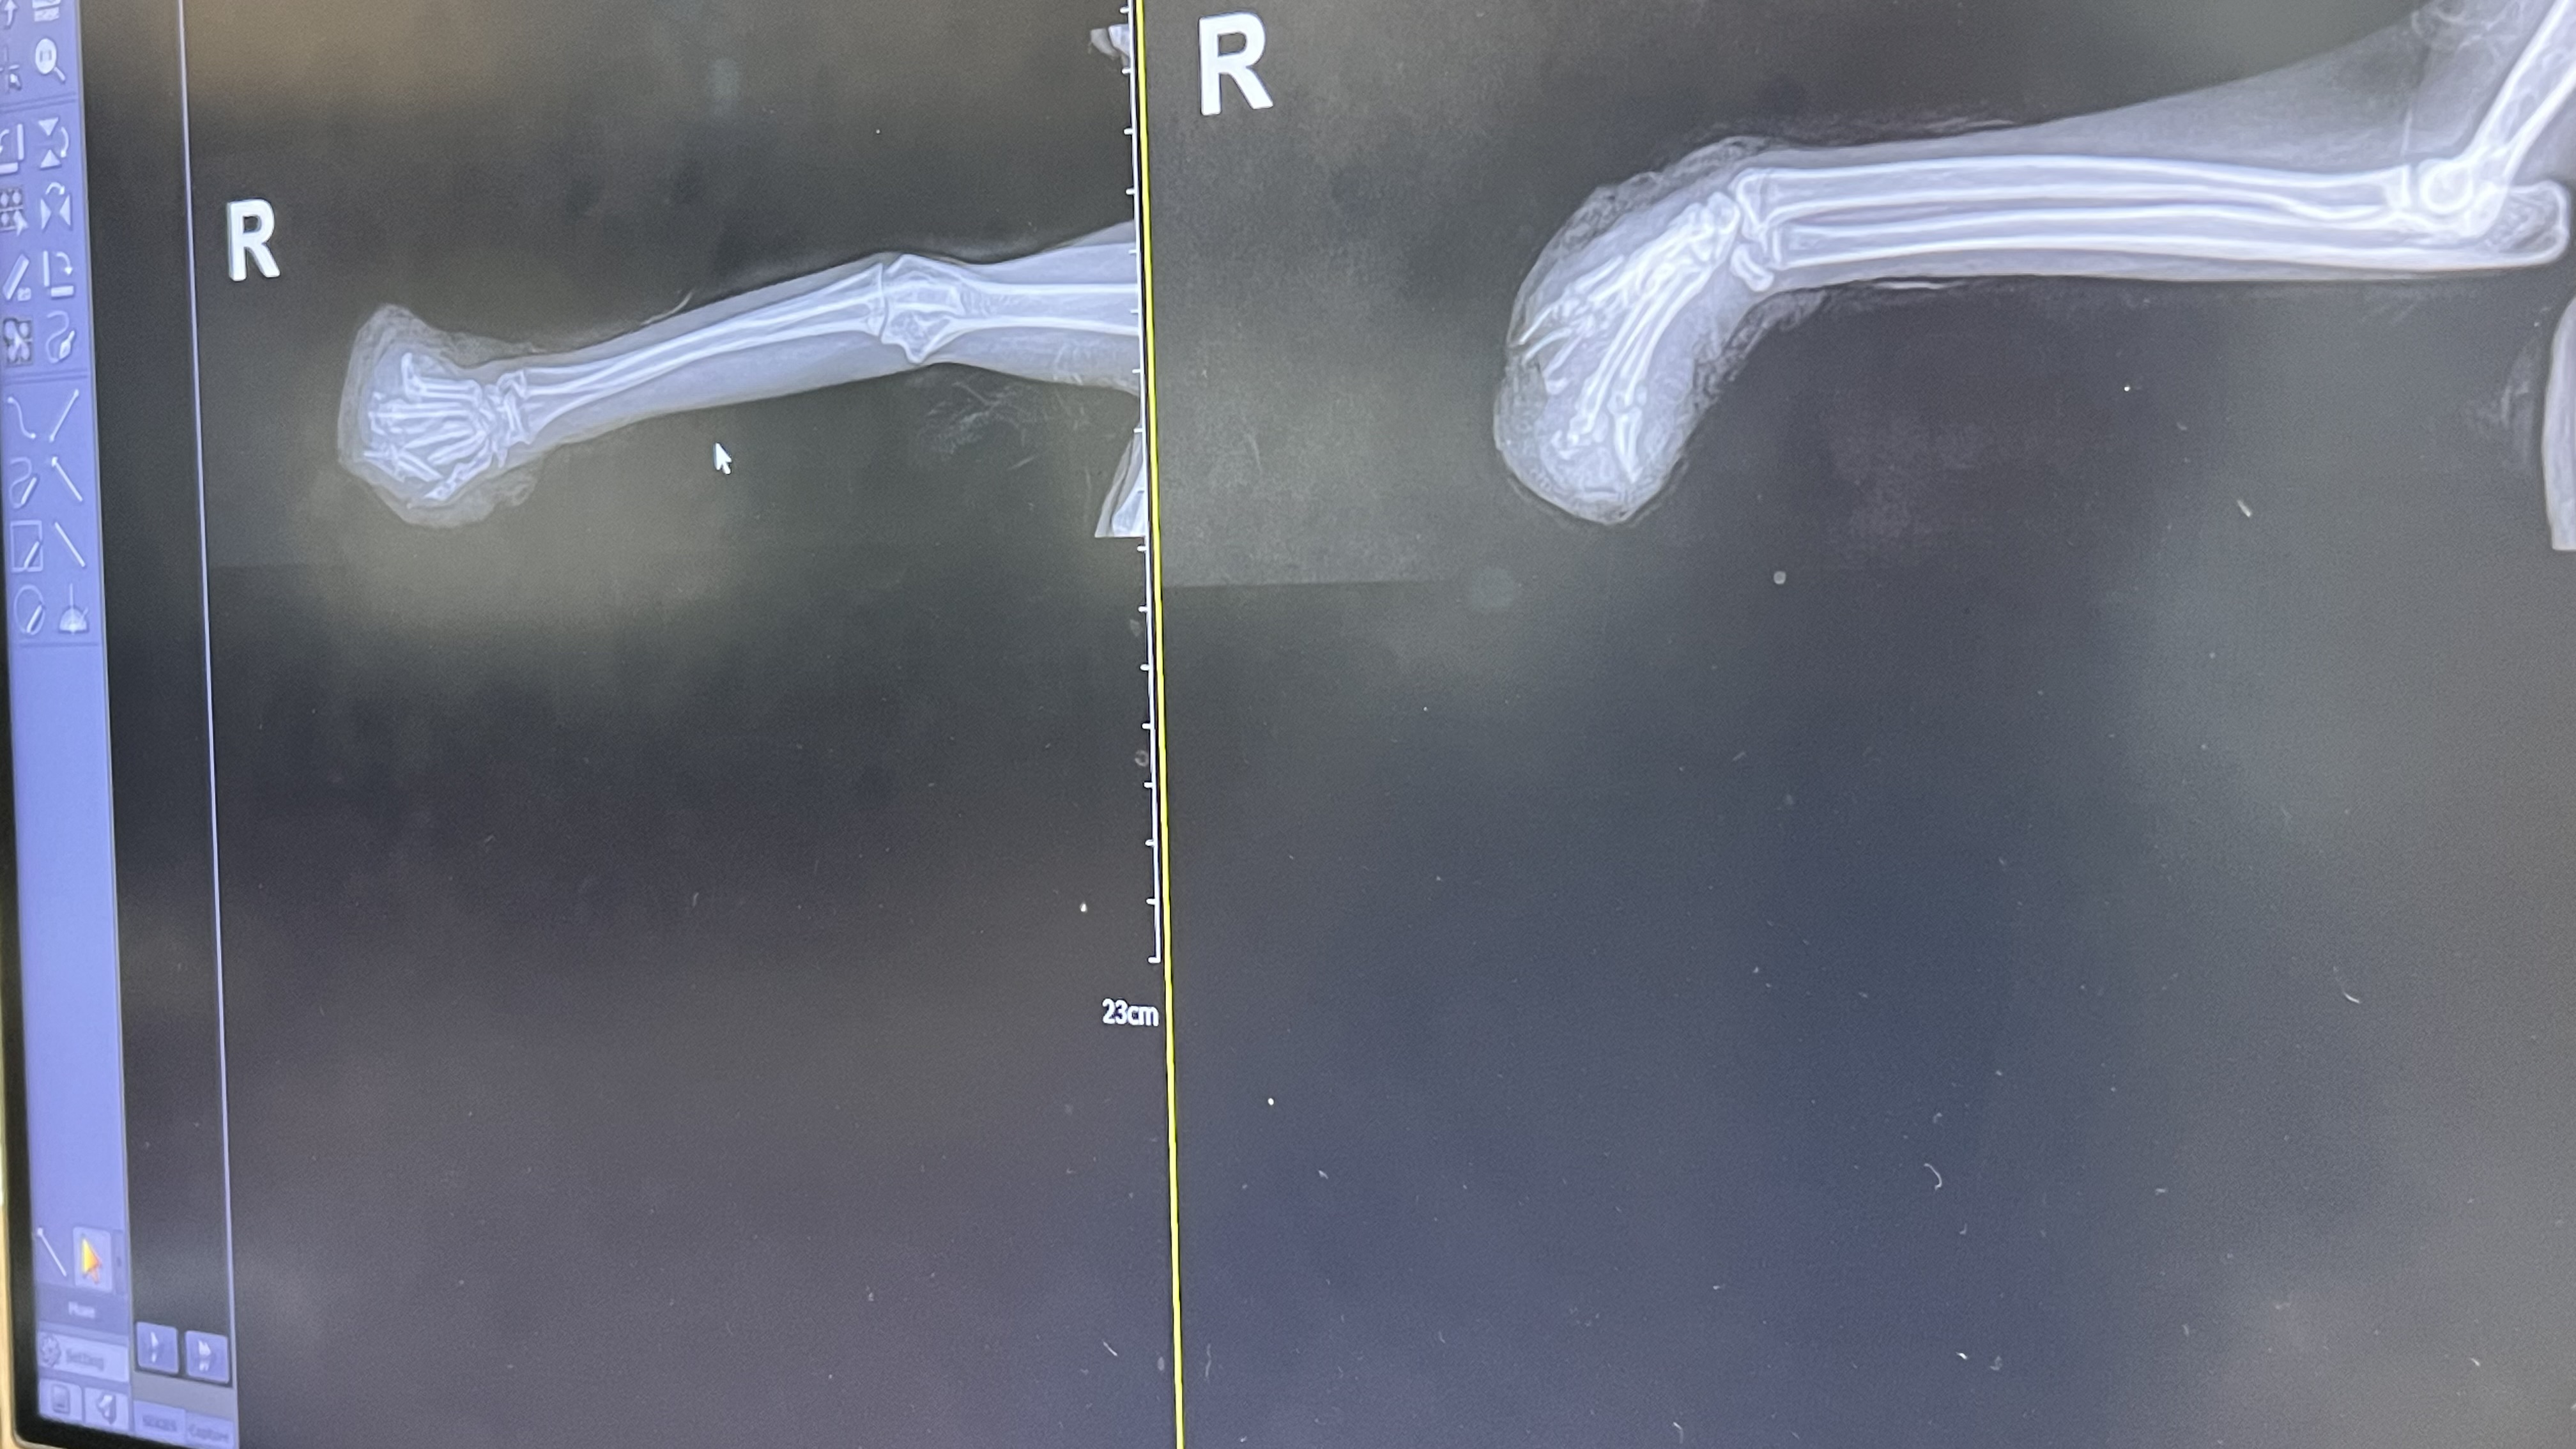

23일에 확실하게 안좋음을 확인하고 25일 아침 7시에 바로 포획하여 병원으로 이동 결과 아이의 발이 다 부러져 조각난 상황이고 염증이 어마 어마하게 부풀어 있는 것으로 보아 시일이 좀 된 것으로 판단된다는 의사쌤의 진단을 들음. 또한 꼬리도 어디선가 상처를 입어 봉합수술이 필요할 정도로 찢긴 상태였음

대상묘 병명 발 전체 부러짐

치료과정 먼저 10월 25일에 여러 시간 상담 후 더이상 발을 사용할 수는 없을 것 같고 워낙 염증이 심해서 발조각을 맞추는 수술은 더욱 어려울 것으로 판단하게 되었음.

카옹이 치료  사진입니다.

치료 후기에 대해 추가 진행합니다. 카옹이는 발이 으스러진 상태에서 오랜 시간 지연이 되다가 보니 조직이 괴사하고 염증이 발보다 더 큰 상태였습니다. 꼬리 부분도 다른 고양이에게 공격을 받은 것인지 아니면 이 또한 차량에 밟혀서 상처가 생긴 것인지 확실하지는 않지만 상처가 크게 벌어진 상태였습니다. 전반적으로 카옹이는 거의 죽어가고 있었습니다. 만약 구조하기로 한 날 구조가 되지 않았다면 카옹이는 죽었을 것 같다고 하더라구요.  의사 선생님의 가장 큰 고민은 아이의 발을 어깨부터 자를 것인지 발목만 잘라도 될 것인지였는데 결국 선택은 발목 절단 수술이었습니다. 카옹이가 이미 성묘였기 때문에 어깨부터 다리를 잘랐을 경우 자칫 다리가 아직 있다는 느낌을 계속 가지고 갈 수 있고 그러다가 다리가 수술을 했음에도 불구하고 계속 아프다는 느낌을 가져가는 경우도 있다고 하더라구요. 게다가 걸을 때도 다리 전체가 없는 것과 발목만 없는 것은 어마어마한 차이가 있구요. 수술이 잘 끝나고 쎈 진통제를 계속 수액과 함께 맞으면서도 많이 아픈지 제대로 먹지도 않고 엄청나게 공격적이었습니다. 오죽하면 카옹이 입원장 앞에 흰색 글씨로 '매우 사나우며 튀어 나올 수 있음'이라고 써 있었겠어요. 하지만 약 2주가 지나고 어느 정도 회복이 되면서 카옹이는 엄청나게 착한 원래의 성격으로 되돌아와 있었습니다. 카옹이의 무사 수술과 치료에 대해 너무 너무 감사하는 마음입니다.

IMG_9207.JPG

IMG_9208.JPG

IMG_9209.JPG